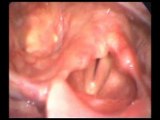

Vidéo issue du logiciel d'orthophonie VOCALAB (disponible sur www.gerip.com). Cette vidéo montre en gros plan des cordes vocales souffrant d'une pathologie.